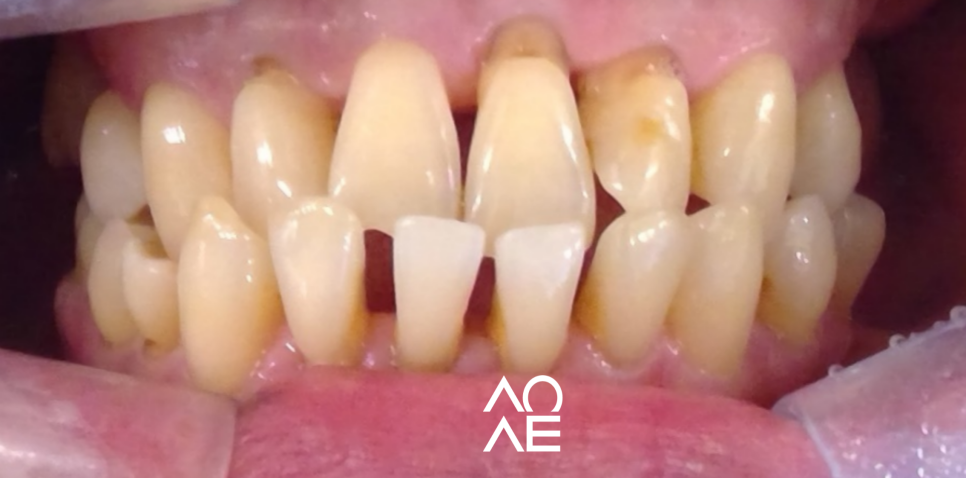

저희 잠원동 치과에서 치료를 받으신

환자분의 소개로 "일본"에서 오신

환자분이신데요.

실제로 나이도 조금 많으셨고,

외국에서 오셨기 때문에 시간적인 제약

내원 횟수에 대한 제약이 분명히 있으셨어요.

교정을 하기엔, 매달 방문하시기도 어렵고

더욱 중요한 것은 환자분의 상태죠

방사선 검사 등을 꼼꼼하게 진행해보니

교정이 아닌 크라운으로 치료가 가능한

구강 상태를 가지고 계셨기에 크라운 치료를

결정하고 진행하게 되었습니다.

| 치료 전(23. 12. 03) | 치료 후(24.06. 20) |